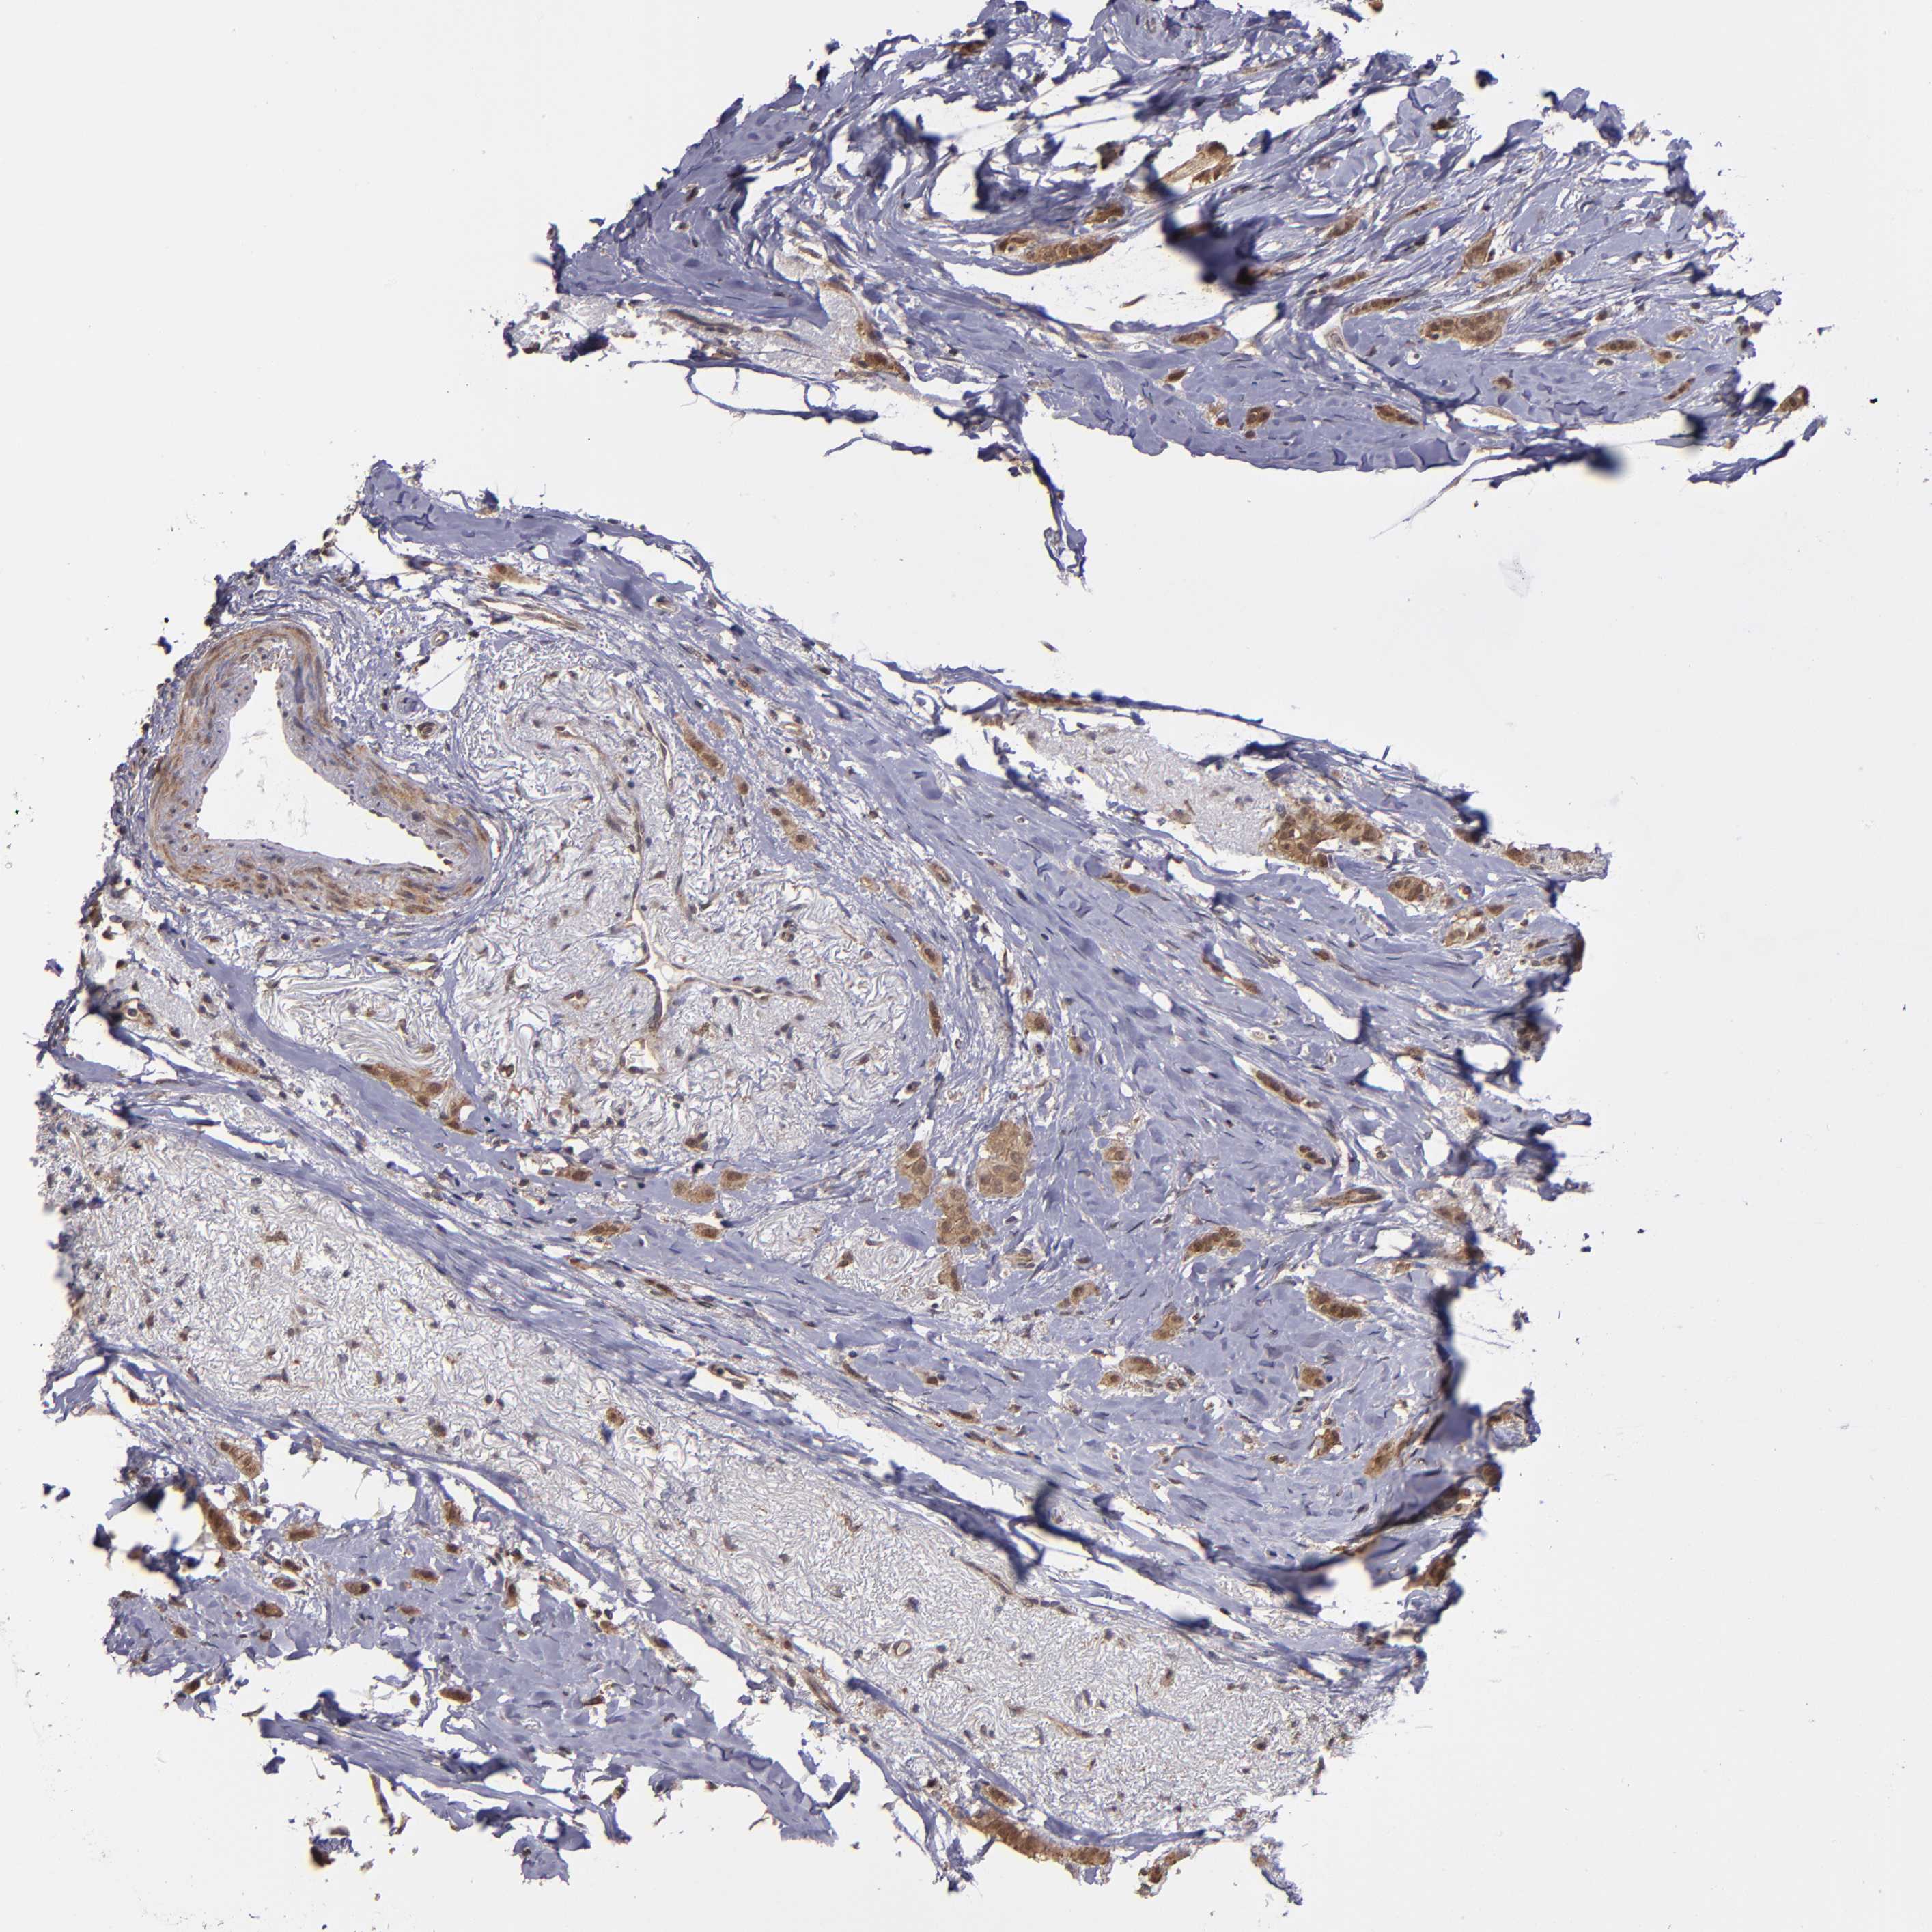

BRCA TCGA BRCA VALIDATION PROTEIN EXPRESSION